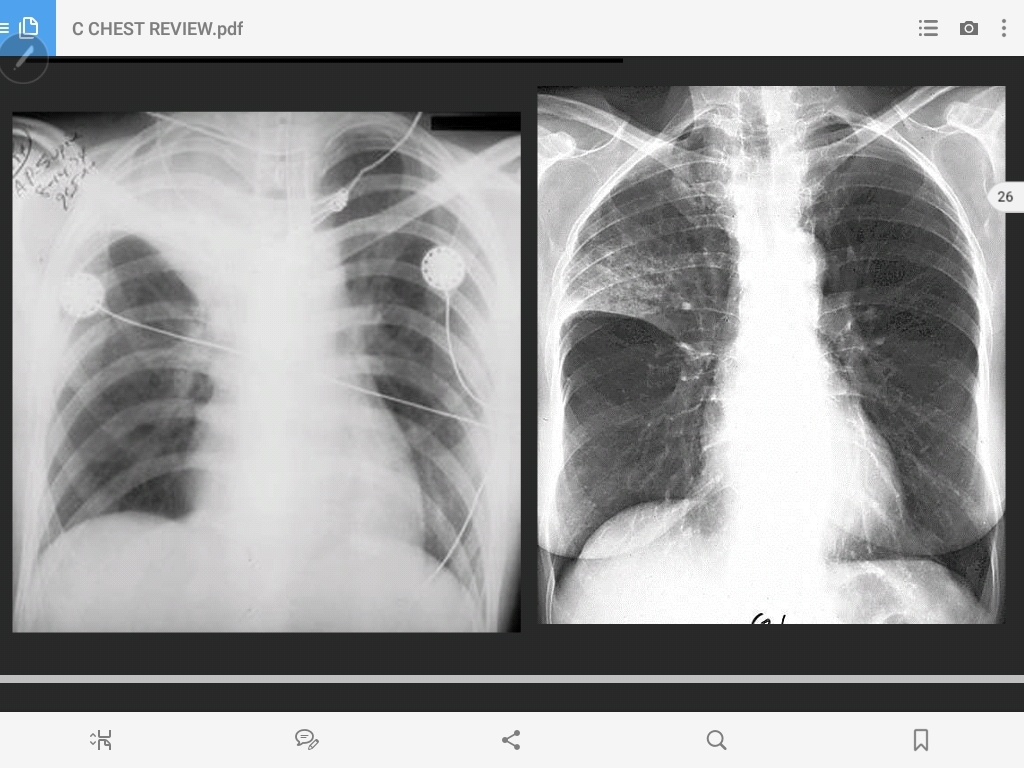

pneumothorax